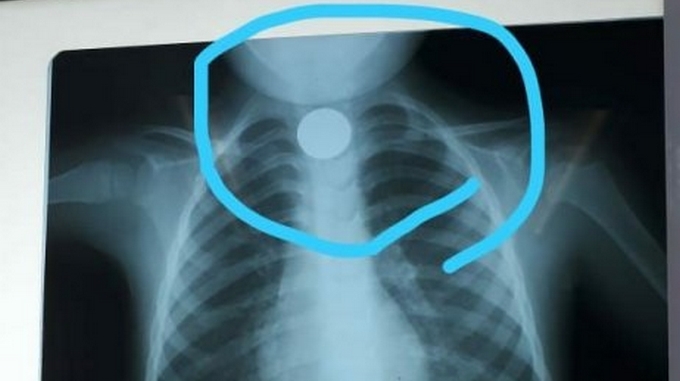

Niño de 3 años se tragó una moneda que quedó atorada en su garganta

En medio de un descuido por parte de los padres, un niño de 3 años se tragó una moneda de 1.000 guaraníes paraguayos, la cual se quedó atorada en su garganta, evitando que pudiera comer o tomar líquidos. Según relató el padre del menor en una entrevista, este se encontraba reposando en otra habitación, recuperándose […]

En medio de un descuido por parte de los padres, un niño de 3 años se tragó una moneda de 1.000 guaraníes paraguayos, la cual se quedó atorada en su garganta, evitando que pudiera comer o tomar líquidos.

Según relató el padre del menor en una entrevista, este se encontraba reposando en otra habitación, recuperándose de una operación, mientras la madre estaba cocinando, en este momento el niño se encontraba viendo televisión y encontró una moneda que decidió probar.

Luego de esto el niño comenzó a vomitar mucho y quejarse del dolor de garganta, lo llevaron al hospital de su localidad pero en este no tenían los implementos requeridos para retirar el objeto por lo que fue remitido al un hospital en San Lorenzo donde fue estabilizado y atendido por deshidratación.

El menor tuvo que esperar alrededor de 1 día con la moneda en su esófago debido a que el único quirófano de pediatría del lugar se encontraba atendiendo otro casos más urgentes de niños con riesgos para su vida.